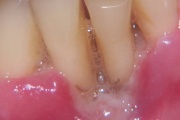

Igemed

Krooniline parodontiit

ANUG (äge nekrotiseeruv haavandiline gingiviit/parodontiit)

Parodontiit